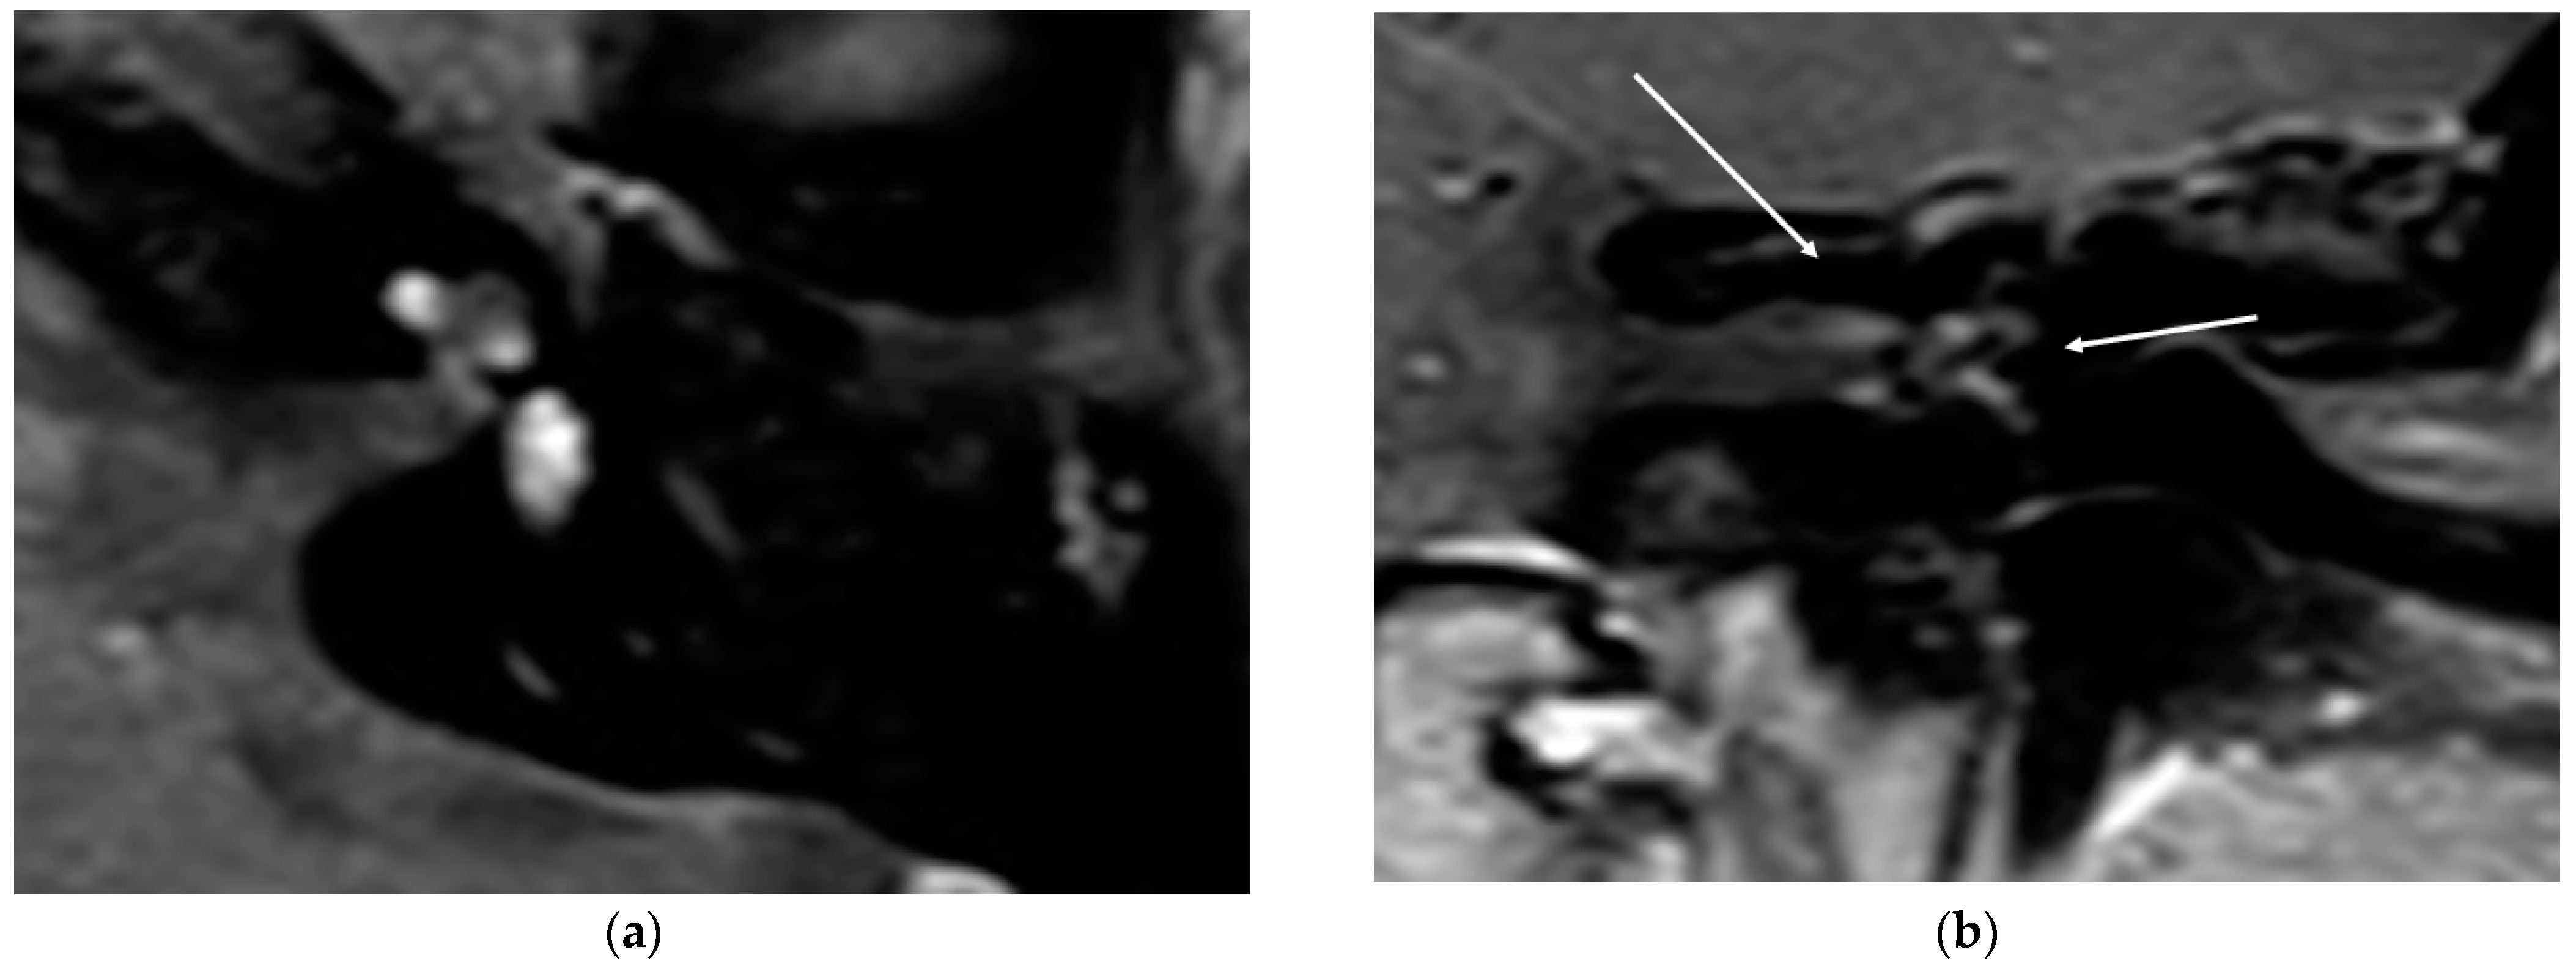

In all cases, the cochlea and the IAC were visually accessible. In all cases, complete removal of the intracochlear ILS vestibular parts was confirmed by the MRI. The individual pre- and postoperative MRI T1 Gad figures are exemplary for case 4 and 6 (Figure 2 and Figure 3). In Figure 4b, an initially radiologically missed or residual tumor at the IAC fundus from the vestibulum (transmacular) is shown (case 5), as well as an additional signal in the basal turn.

Figure 4.

(a). An exemplary ILS tumor pre-op (T1, Gad). (b). The ILS region with a T1 Gad sequence after removal and CI and detection of a possible tumor in the IAC and in the basal turn.

In this series, through MRI evaluation after a period of 13.4 months, we observed no residual tumor in the area of interest behind the modiolus. In one case, we observed a T1 signal at the upper part of the IAC, indicating a transmacular form. This case needs to be further evaluated in detail to control further growth in the future. For this patient, it remains unclear if the tumor was located in this area before the surgery and was not observed due to the slice thickness of 2 mm or if it was a residual tumor with a fast-growing tendency. The fact that a visual tumor was not observed intraoperatively led us to assume that a partial, very small ingrowth under the radiological visual resolution of 2 mm was persistent preoperatively. Very small areas of ingrowth into the modiolus and the IAC have been described histologically [28]. The additional small signal in the basal turn can be interpreted as a residual tumor.